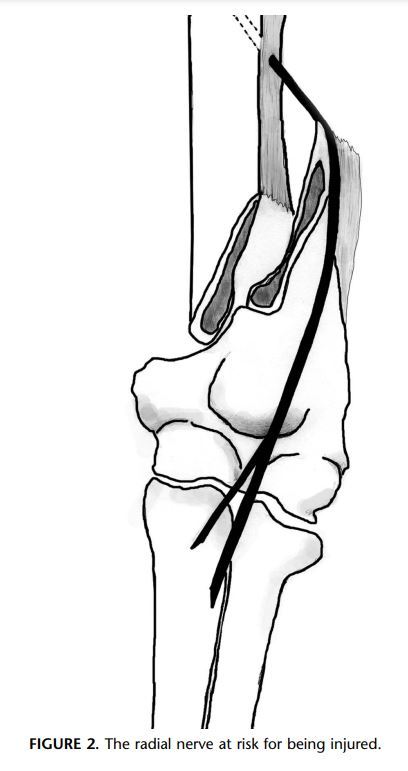

Define Holstein-Lewis fracture? How does it occur

A

The Holstein-Lewis fracture describes a type of humeral fracture

• that is, a simple spiral fracture in the distal third of the shaft

• with the distal bone fragment displaced proximally and the proximal end displaced radially

• with resultant displacement of intermuscular septum

• High association with radial nerve palsy was that the fracture occurs at a point where the radial nerve runs through the lateral intermuscular septum (as opposed to lying in direct contact with the bone) and thus has limited mobility.

• Due to the force of the injury, this potentially lacerating or trapping the radial nerve